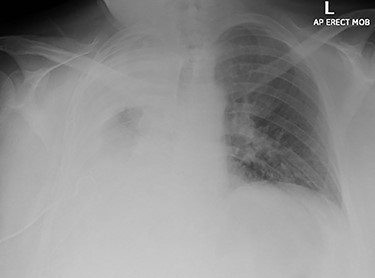

A 60-year-old smoker and obese patient (body mass index: 38.8), with a past medical history of well-controlled hypertension, hypercholesterolemia, Type 2 diabetes and mild lymphocytosis, namely, white blood cell count was 25.67 × 109/l and the lymphocyte rate was 7.60 × 109/l (diagnosed 7 years ago without any further investigation), was admitted to the local hospital complaining of significant shortness of breath and persistent continuous dry cough. Both were present at rest and exacerbated with minimal activity, resulting in decreased ability to formulate a sentence properly. A chest X-ray revealed complete consolidation of the right lung field (Fig. 1). A chest tube was inserted, draining in total 3.8 l, resulting in significant improvement of the patient’s symptoms. Pleural fluid cytology showed lymphocytic effusion with no evidence of malignancy. The chest computed tomography (CT) scan revealed consolidation of the right upper lobe with a 6-cm lesion in the hilum completely occluding the right lower lobe bronchus (Fig. 2). The right upper and middle lobe bronchi could not be reliably visualized either.

Chest X-ray imaging of the patient during admission; a wide right sided pleural effusion is depicted.